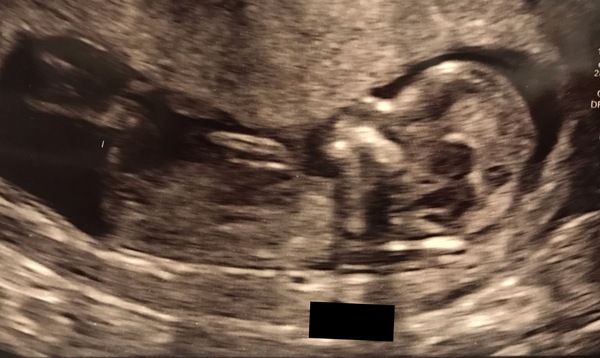

Finally had my first scan today. Dated at 13w2d with a EDD if 22 June.

I'm High risk due to a kidney condition so will have scans and consultant appts at 28 32 36 weeks plus monthly renal function tests. Was as the hospital 2.5 hours today!

MIL died suddenly in Friday so the scan was bitter sweet. I cried as the baby will never know their grandma and dh struggled to hold it together for me. It's a twinkle of positivity to keep us going but we are too shocked and upset to feel excited at the moment.